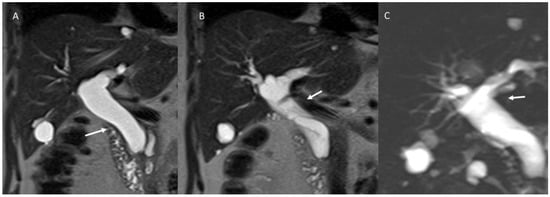

6.2. Intraductal Papillary Neoplasia of the Bile Duct

6.3. Intraductal Tubulopapillary Neoplasms of the Bile Duct

6.5. Diagnostic Management